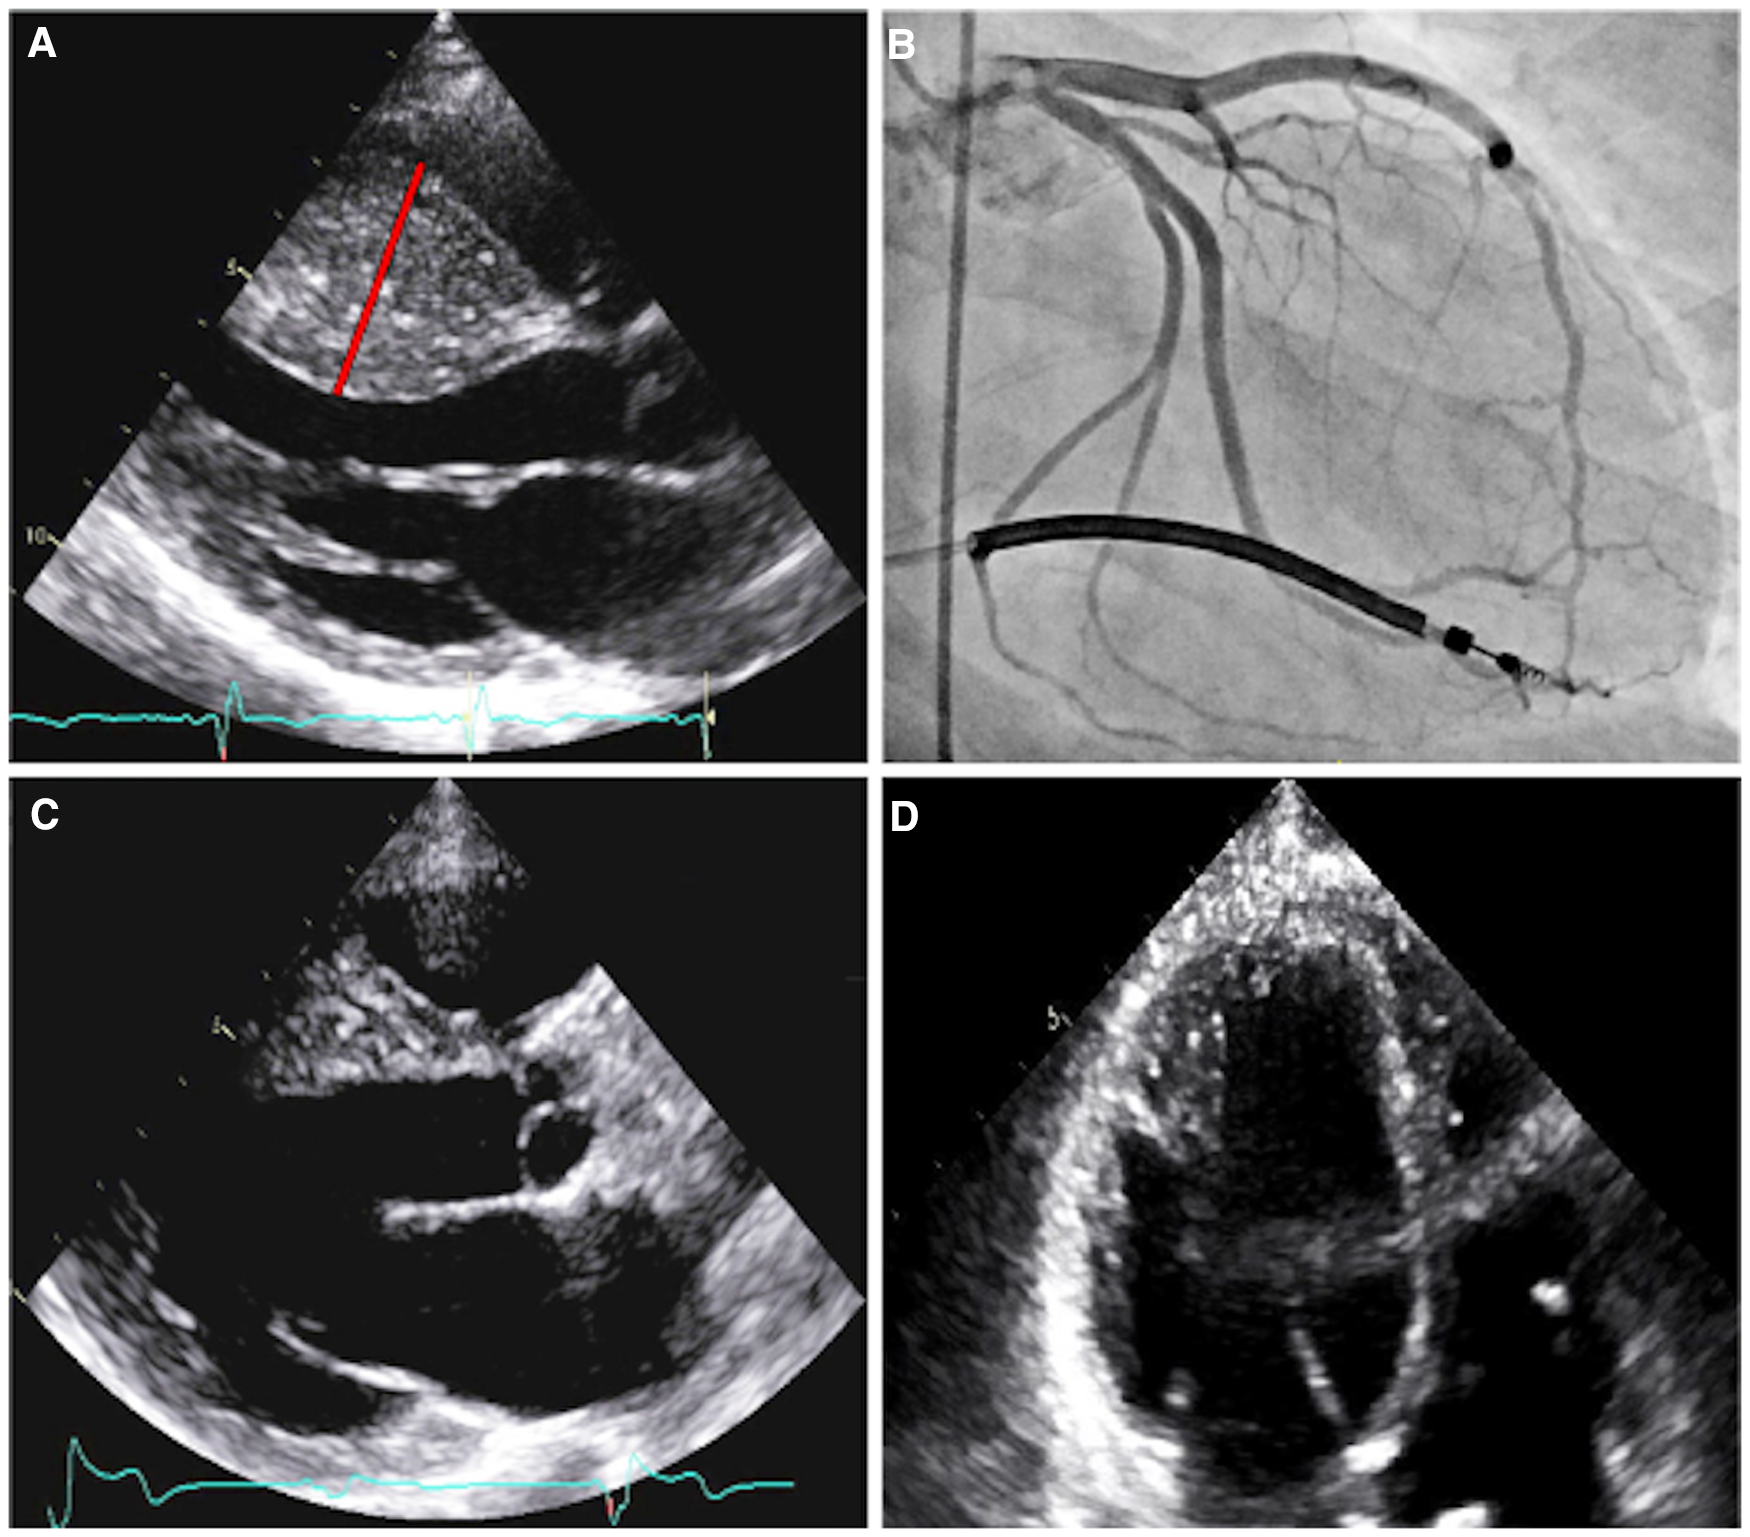

Figure 2

Imaging of patient A. Parasternal long axis echocardiogram prior to septal myectomy (A). The interventricular septum has reverse curve morphology, with a septal thickness measurement of 33 mm (red line) during diastole and a patent left ventricular outflow tract. Right anterior oblique caudal angiogram with prominent myocardial bridging of the large first and second septal perforators (B). Parasternal long axis echocardiogram, status-post septal myectomy (C). Four-chamber echocardiogram, with increased apical cavity size following septal myectomy (D).

Patient A was initially referred for cardiac evaluation when she experienced a sudden out-of-hospital cardiac arrest at age 18. She was swing dancing with friends when she suddenly lost consciousness and was found to be pulseless. Bystander cardiopulmonary resuscitation was performed for eight minutes. On-site automatic external defibrillator advised no shock. She regained full neurological function during hospitalization with a hypothermic protocol. Serial 12-lead electrocardiograms (ECGs) demonstrated left ventricular hypertrophy with ST-T depression in the anterolateral leads, with an initial QTc interval of 510 msec that normalized throughout the course of hospitalization. Transthoracic echocardiography revealed HCM with massively hypertrophied left ventricular septum (33 mm) with a reverse curve septal contour (Figure 2A). There was no outflow tract obstruction at rest or with Valsalva maneuver. She underwent single-lead implantable cardioverter-defibrillation (ICD) placement and was started on metoprolol succinate 25 mg daily.

Coronary angiography revealed marked myocardial bridging of large septal perforators (Figure 2B and Supplementary Video S1). She ultimately underwent coronary artery unroofing and extended septal myectomy through combined transaortic and transapical approaches to improve diastolic function and debulk her arrhythmogenic substrate (Figures 2C, D). Pathology demonstrated histological features consistent with HCM, including moderate to marked myocyte hypertrophy, mild to focally moderate myocyte disarray, and mild to focally moderate interstitial fibrosis. Flecainide was discontinued and sotalol (120 mg twice daily) was resumed on post-operative day four.